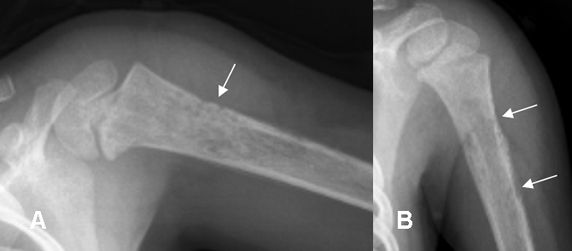

Fig 28. Osteomielitis.

A y B: Rx simple. Prominencia de tejidos blandos, irregularidad en la cortical del húmero y alteración en la densidad del hueso, por osteomielitis.